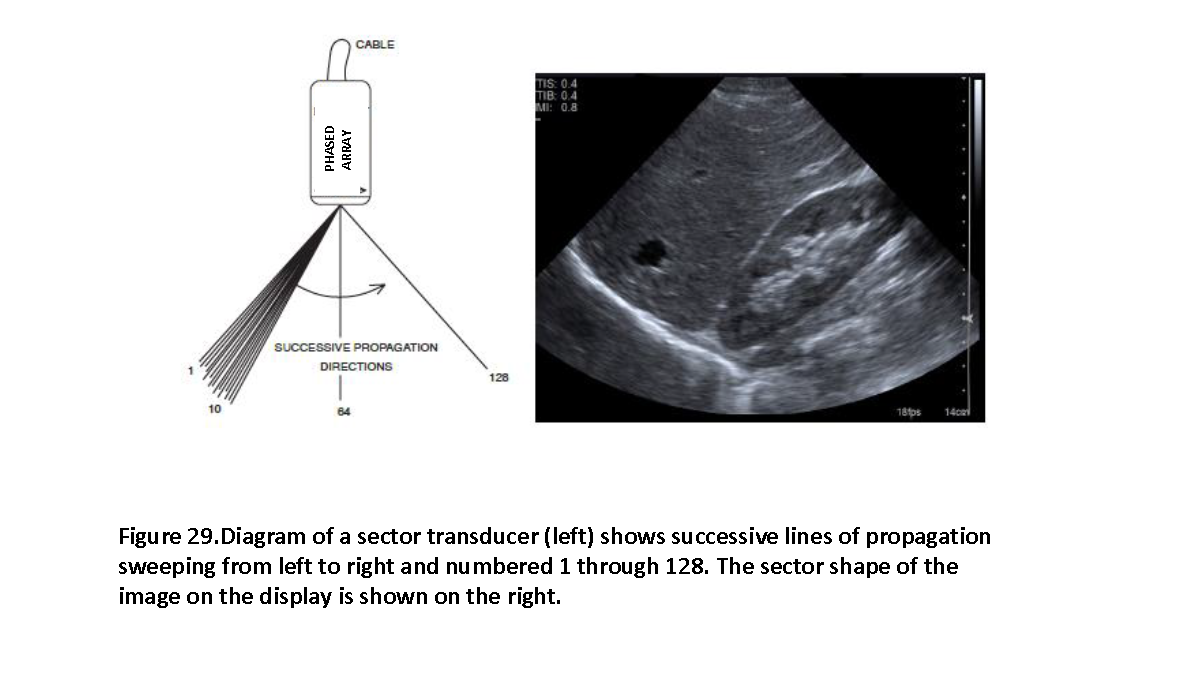

A beamformer is a method of adjusting, combining, or processing waveforms going into or received from an array of transducer elements to shape and direct an ultrasound beam. (see Figures 10, 29, 30 and 35)

A method of image display in which the amplitude envelope of the echo signal is represented by modulation of the brightness of the corresponding image point. The position of the echo, displayed in the scan plane, is determined from the position and angulation of the beam and the transit time of the acoustic pulse (see Figures 29 and 30).